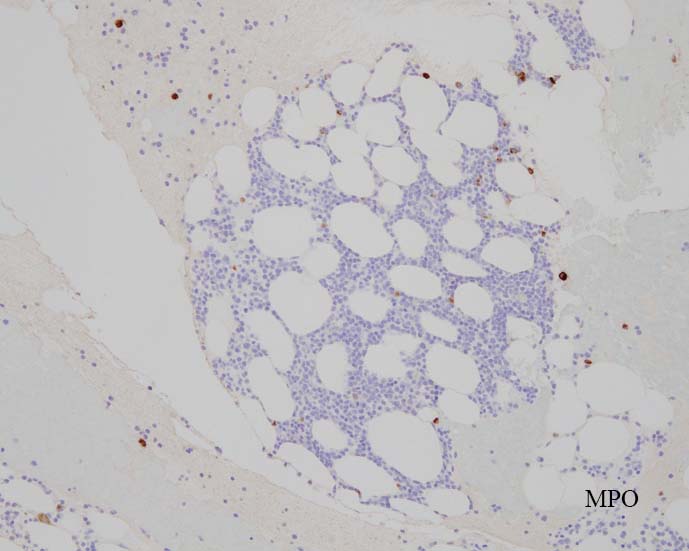

blastic cellsは, CD45+, CD34+, CD38+, TdT+, CD7+, HLA-DR+, CD123+. cCD3-, sCD3-(FCM), CD20-, CD19-とCD79a-(?) (plasma cellが陽性でIHCでは判定が難しい), MPO-.

CD3-, CD79aは増加しているplasma cellsが陽性で判定が難しい. CD10-, MPO-. (CD10は画像欠)